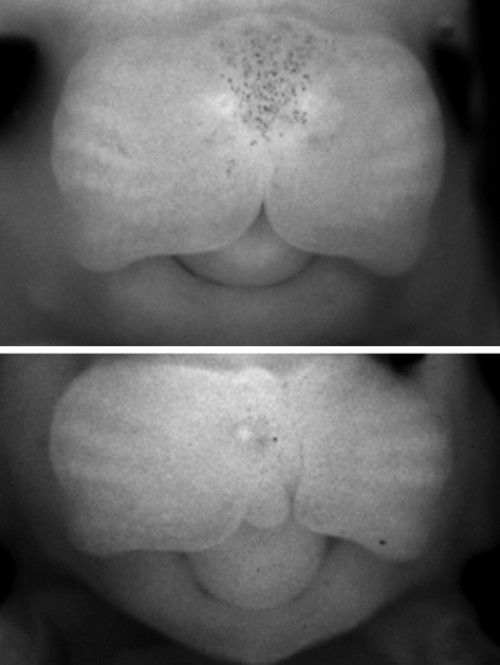

唇腭裂是一个通俗的说法,它是指在人的是唇和颚部有裂口。其实这个名称并不能代表颅面部全部先天畸形。还包括牙槽突裂,另外还有有效性的唇裂还包括鼻底的裂开。再有由于牙槽突裂的存在,还会导致牙齿在发育当中的一个畸形。这种畸形它会影响到口腔和面部的很多的器官和功能。另外由于腭裂存在,还会影响到患者的听力。因此唇腭裂畸形是系统性、可能会影响多个方面的病变。这种病变一般来说是由于在发育过程中,由某种因素而导致形成口腔和面部发育的一些生发中心没有正常的连接和融合所导致的。唇腭裂是一种非常常见的先天的颌面部的发育畸形,一般来说在正常人群里面就达到1-2‰。亚州人群高于非洲人群。或者是600-700个人当中就会有一个唇腭裂小孩的发生。这种唇腭裂会在妊娠前的前三个月就出现,由于各种各样的因素,而影响胚胎的发育。这种畸形会影响到我们小朋友,除了形态和功能以外,它的影响还是非常深远。包括未来的发音,还有颌面部骨骼的发育,还有外形和功能的一些畸形和不正常。还有可能会影响到他参与社会行为,一些社会交往,反过来还会影响他的心理发育。因此这种唇腭裂的畸形是需要我们特别关注的。在胚胎发育的早期,唇、腭是由两侧组织往身体中线融合起来的,若不能正常融合,就会产生各种不同部位的裂缝,单纯嘴唇裂开,称为唇裂,既有唇部裂开又有腭部裂开称为唇腭裂,有时仅口腔内腭部裂开而外部正常,则称为腭裂。

在胚胎发育的早期,唇、腭是由两侧组织往身体中线融合起来的,若不能正常融合,就会产生各种不同部位的裂缝,单纯嘴唇裂开,称为唇裂,既有唇部裂开又有腭部裂开称为唇腭裂,有时仅口腔内腭部裂开而外部正常,则称为腭裂。